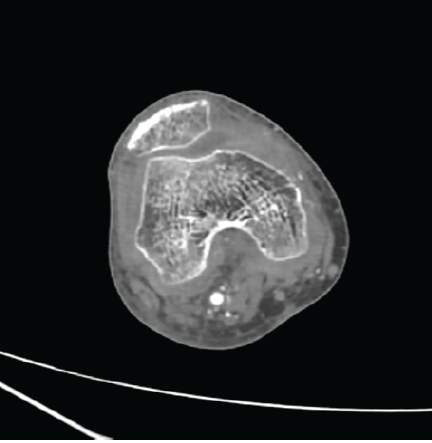

Follow-up computed tomography (CT) angiography at 24 h showed complete obliteration of the lesion with preservation of distal arterial flow (Fig. 5).

Figure 5: Computed tomography angiography of the right knee performed 24 h after ultrasound-guided compression demonstrating complete obliteration of the superior medial genicular artery pseudoaneurysm, with no residual contrast filling and preserved distal arterial flow.